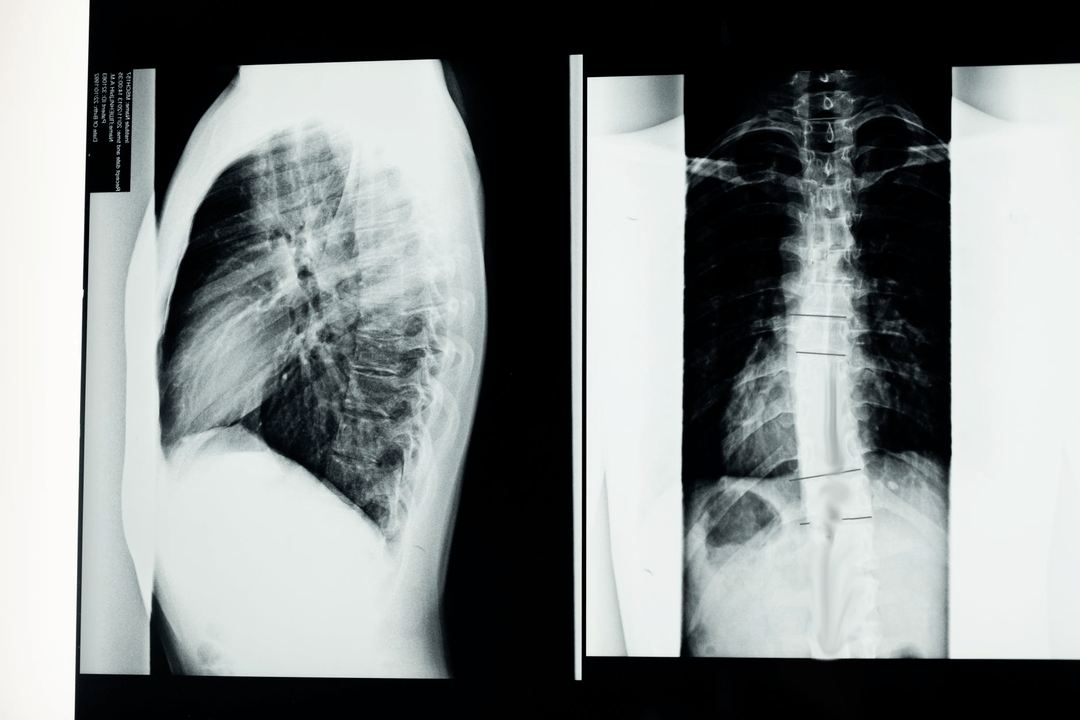

Bevor mit diagnostischen Studien begonnen wird, erhebt der Neurologe die Krankengeschichte des Patienten und untersucht sorgfältig seine Beschwerden. Osteochondrose weist bei einigen anderen Krankheiten gemeinsame Symptome auf, daher ist es wichtig, Pathologien unterscheiden zu können. Röntgenuntersuchungen helfen, die Diagnose einer Osteochondrose zu bestätigen: Radiographie, Myelographie und Computertomographie.

Mit einer Übersichtsröntgenaufnahme können Sie ein Röntgenbild der Wirbelsäule oder eines Abschnitts davon anfertigen. Auf diese Weise kann der Arzt den von der Erkrankung betroffenen Ort bestimmen. Zur Verdeutlichung erklären wir, wie eine Osteochondrose mittels Röntgen festgestellt werden kann: Das Bild zeigt eine Verengung der Bandscheibe, das Vorhandensein von Knochenwucherungen (Osteophyten) oder eine Formveränderung des Wirbelsäulensegments.